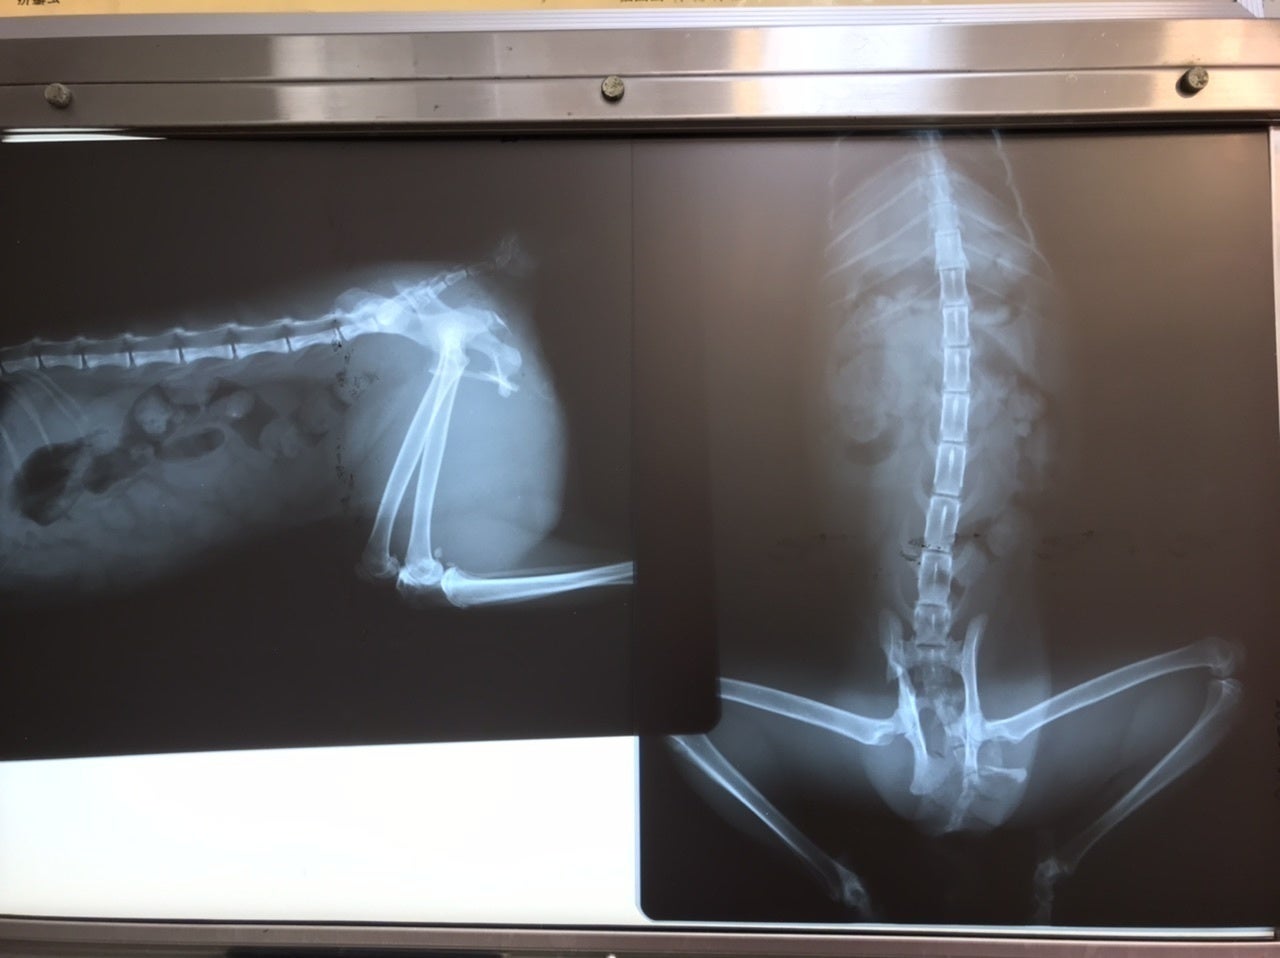

先生は見てすぐに「骨折してる」と仰い、レントゲンを撮ると骨盤が骨折していました。「交通事故だよ」とも仰いました。

また「お腹から折れた骨が飛び出てそれがまたお腹に戻ったんだね。」とも仰いました。

今、壊死してしまった皮膚と化膿している所が広範囲の為、縫合手術はせずに新しい皮膚が下から盛り上がって来るまで毎日皮膚の洗浄をし、点滴や注射をしながら栄養補給をし、皮膚の再生を待ちつつ、今後体力がついてから骨折の手術をするそうです。

ご支援頂いた金額は入院費(1日 5,500円)×入院日数(現在入院中)、通院費、初診料1,650円、診察料(1回)825円×通院日数、処置料550円×通院日数、レントゲン検査費4,400円、血液検査費、猫三種混合ワクチン費6,050円、尻尾切除費11, 000円、骨折手術費110, 000円、骨折手術後の入院費(まだ不明)、点滴料(1回)1,100円、注射料(1本)1,100円、内用薬費、療法食代、避妊手術費25,300円にあてさせて頂きます。

残念ながら尻尾がダメになってしまったそうなので、尻尾の切除手術を行い、体力がついて来てから骨盤骨折の手術を行います。